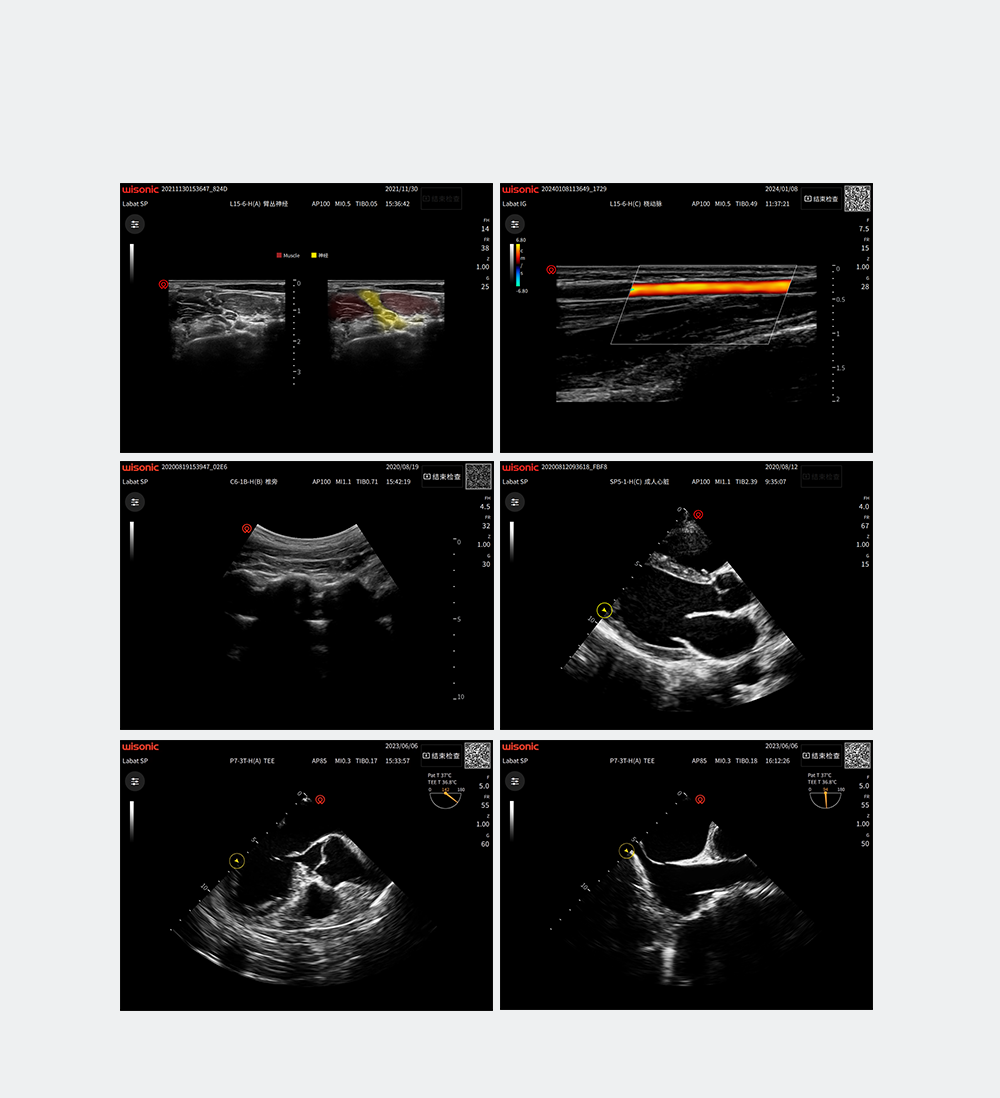

Excellent Clinical Images

Anwendungsbilder